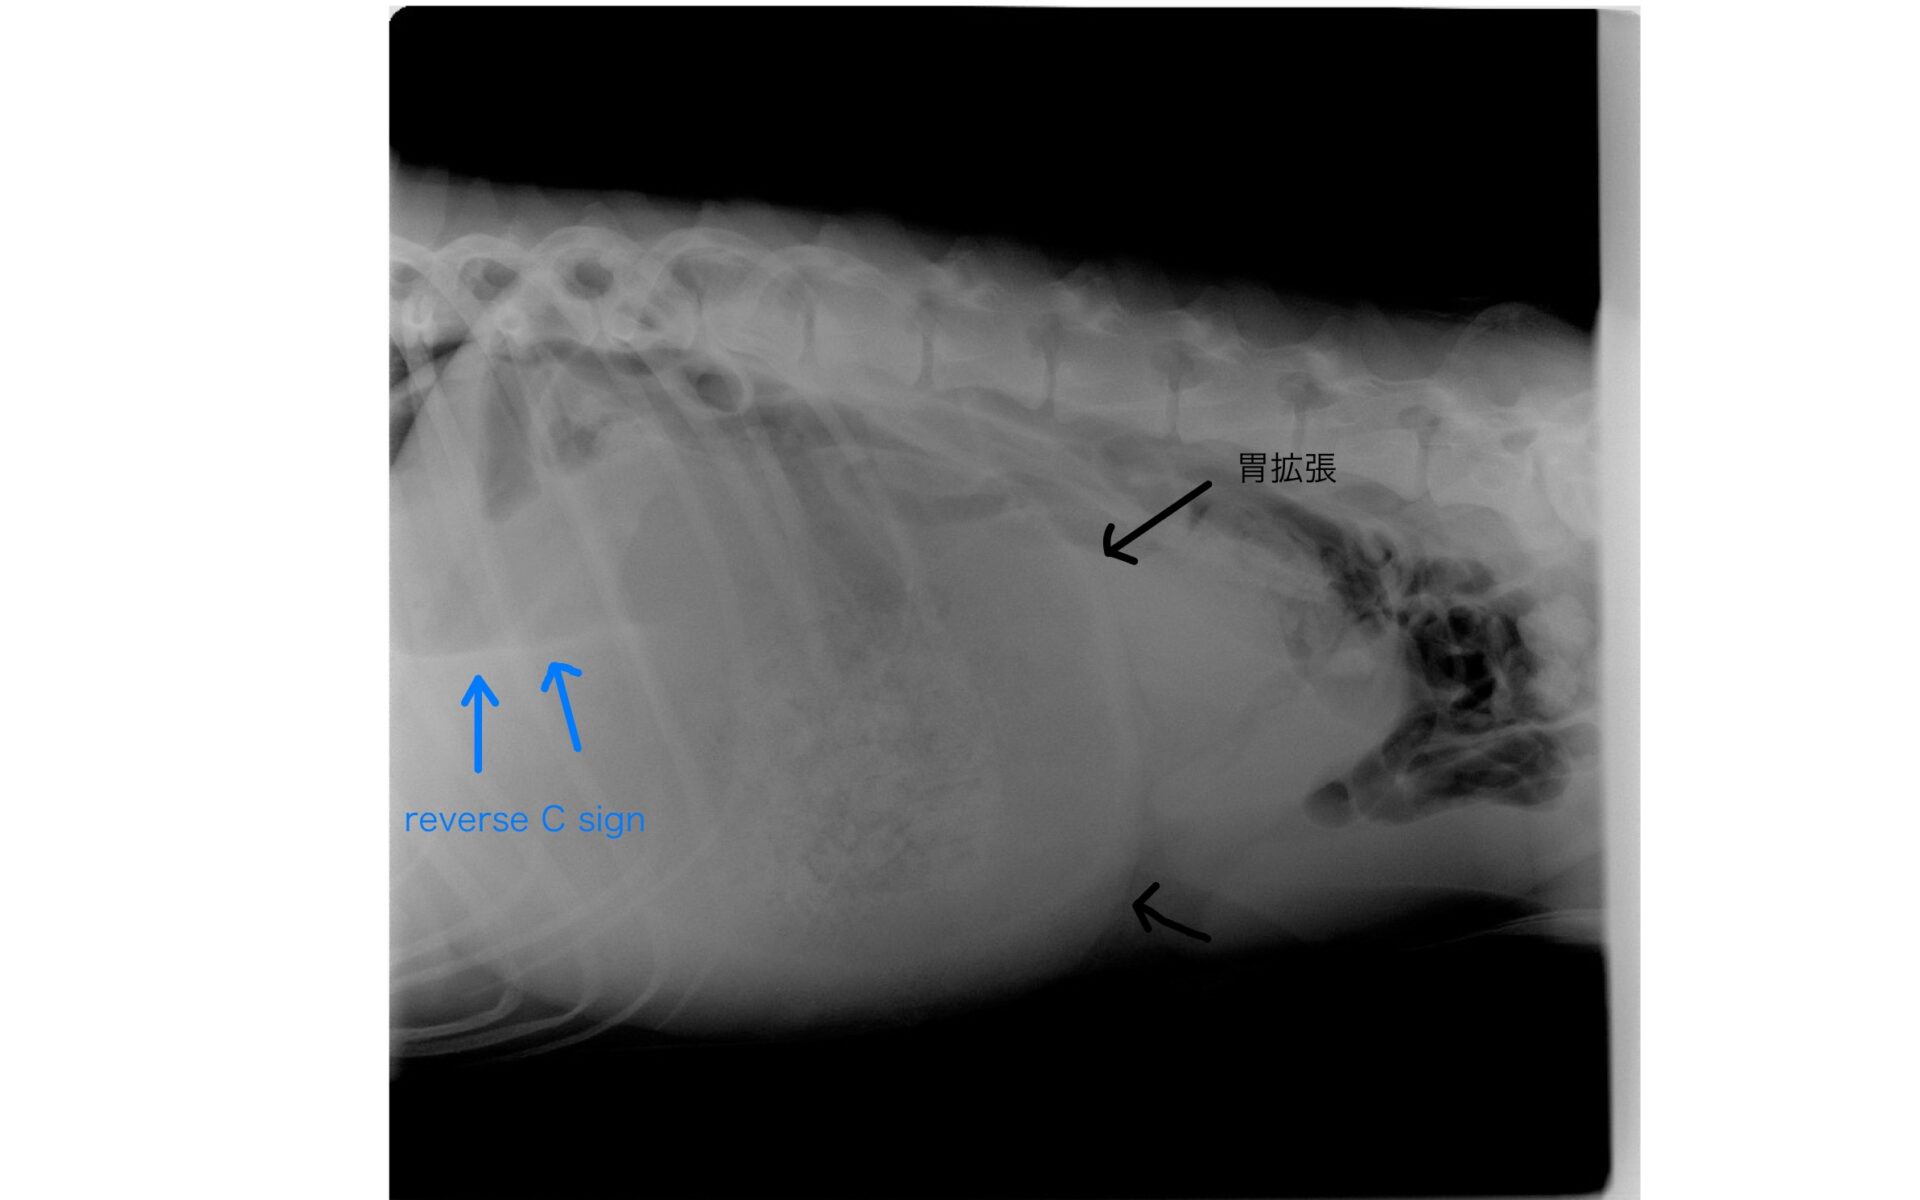

症例紹介